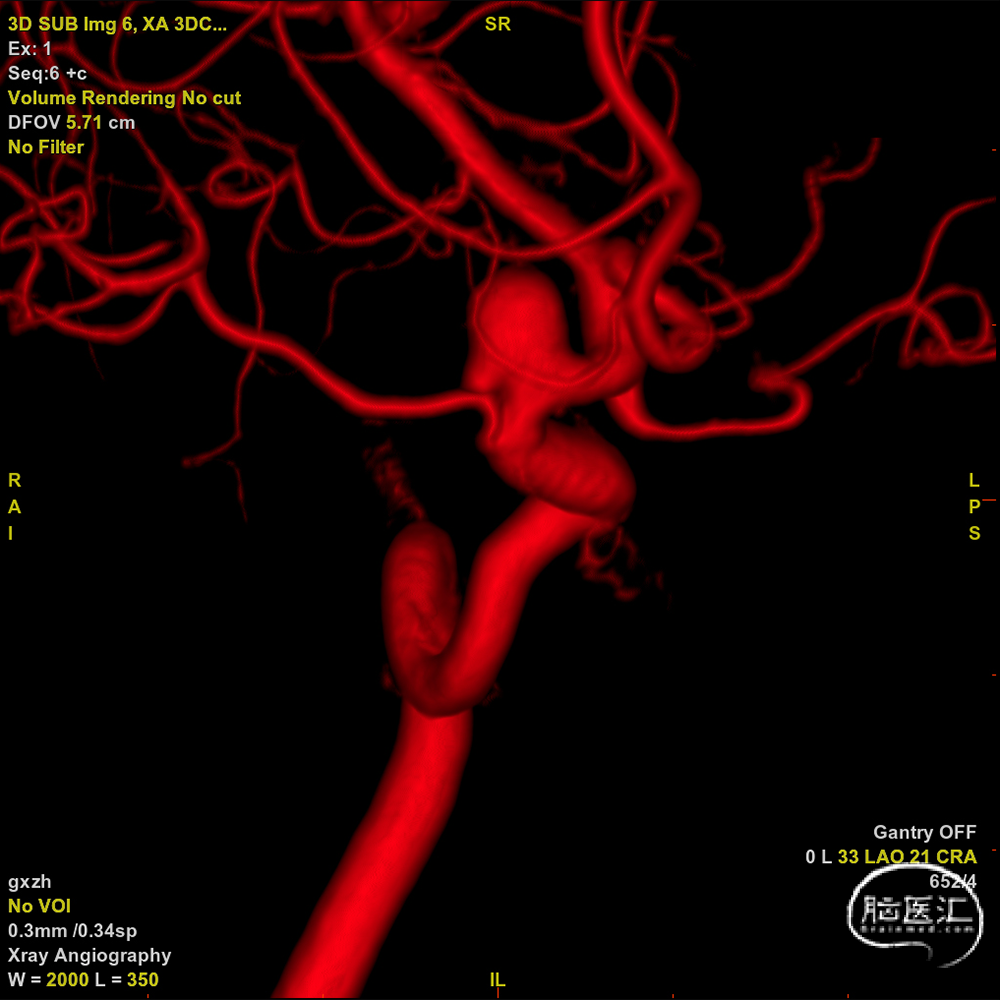

术前影像

DSA左侧颈内

术中工作位造影。

复查造影见动脉瘤腔内造影剂明显滞留,支架位置理想,贴壁良好,载瘤动脉通畅,未见造影剂外渗,远端血管显影充分。

3D-DSA重建结果。